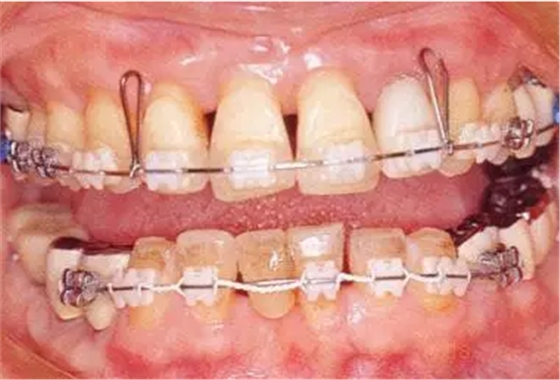

3.png

▲圖19-7

正畸治療完成時。

33.png

▲圖19-8,9

▲圖19-8 佩戴臨時修復(fù)體。即使在這個狀態(tài)下,依然有牙周袋殘留。

▲圖19-9 完成牙周外科治療后的狀態(tài)。